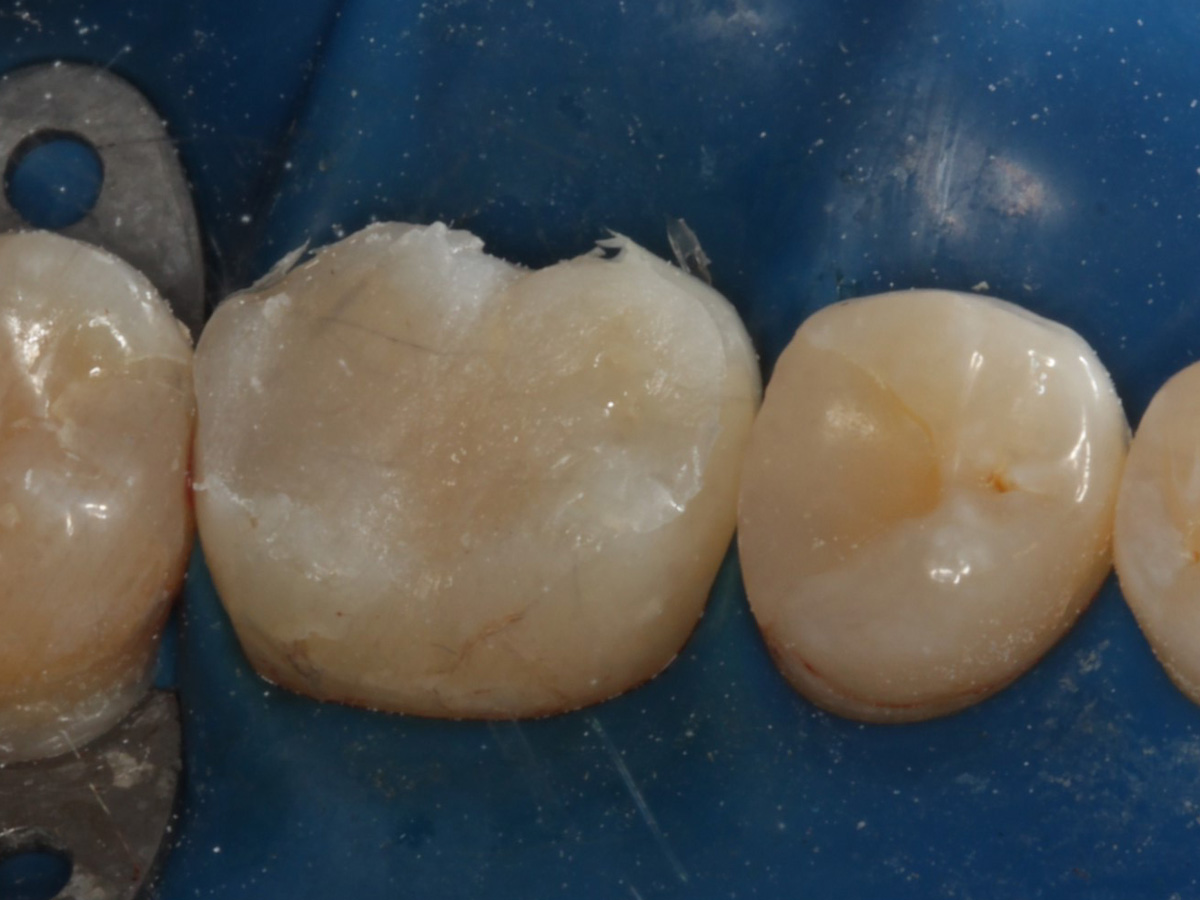

Abbildung 2

Quadrantenisolierung mit Kofferdam (x-heavy)